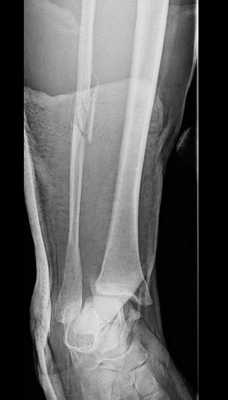

Пациент Д.27 лет, травма в результате неудачного приземления после прыжка старзанки на мелководье. Стопа ушла кнаружи относительно фиксированной голени. Произошёл перелом малоберцовой кости в средней трети с разрывом всех компонентов дистального межберцового синдесмоза и отрывной перелом внутренней лодыжки.

Данный тип переломов лодыжек считается очень тяжёлым и относится к категории 44С2 по классификации Ассоциации Остеосинтеза. Казалось бы, сломаны всего 2 кости, да и переломы по своей морфологии не особо и тяжёлые, почему же данный тип переломов лодыжек считается крайне тяжёлым?

Всё дело в повреждении мягких тканей, прежде всего разрыве всех 4 компонентов дистального межберцового синдесмоза - передней и задней нижних межберцовых связок, межкостной связки и межкостной мембраны. Вместе с отрывом медиальной лодыжки всё это делает перелом абсолютно нестабильным и требует операции в 100% случаев.